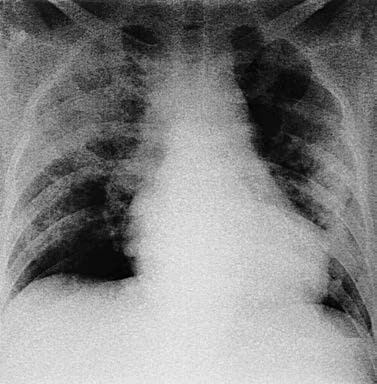

Early x-ray may show no abnormalities or mild interstitial changes, with increased lung markings and hazy edges. This progresses to bilateral patchy or confluent ground-glass opacities or consolidation. The changes are consistent with pulmonary edema, showing rapid variability. Chest x-ray in the late stage may show pulmonary interstitial fibrosis. Although CT is more accurate than x-ray, its high radiation and the high risk of transporting critically ill patients limit its widespread use. Currently, ARDS diagnosis primarily relies on chest x-ray.

Figure 1 Extensive patchy infiltration in both lungs on the chest x-ray